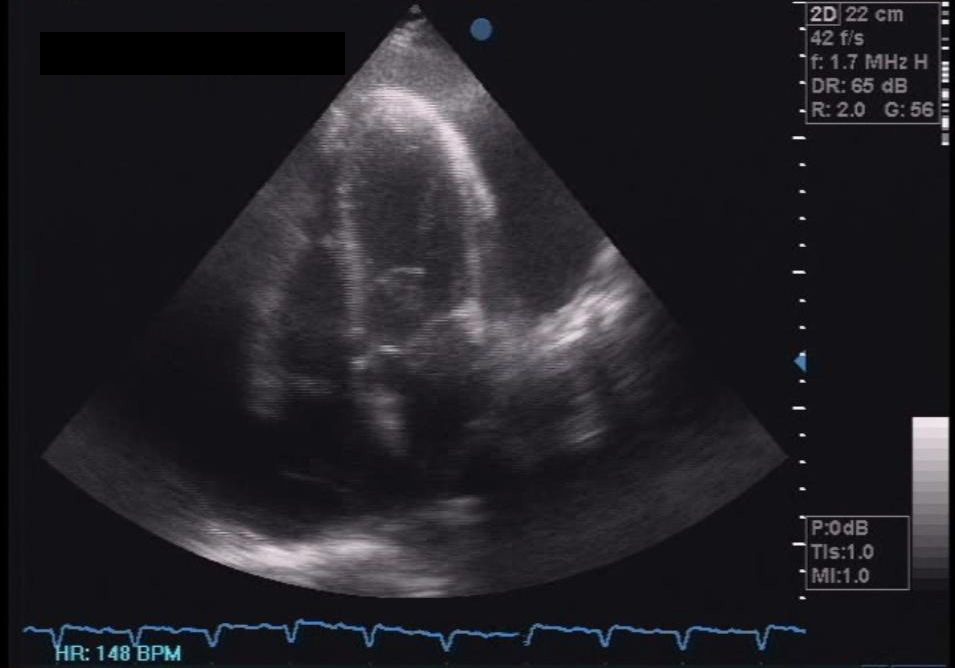

Her 12-lead electrocardiogram showed atrial fibrillation in rapid ventricular response, with nonspecific ST-T wave changes. A 2D echocardiogram with color-flow Doppler during the second admission showed normal-sized chambers with left ventricular remodelling and mildly depressed left ventricular systolic function; adequate right ventricular systolic function; mild to moderate pulmonary hypertension; and massive pericardial effusion in impending tamponade (Figure 3). Pericardial fluid samples were sent for differential cell counts, cytology, acid-fast (AFB) and conventional gram stain and culture, tuberculous polymerase chain reaction (TB PCR) and determination of glucose and total protein levels. Table 1 summarizes the pericardial fluid analysis.

Click here to download Figure 3Figure 3. Initial 2D echocardiogram showing circumferential pericardial effusion with suspicious right ventricular collapse during late diastole, a sign of tamponade.